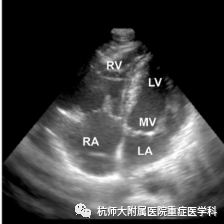

c.心尖四腔心切面:位置选择:心尖处,超声探头声束朝向患者右肩方向指向心底;操作过程中在胸骨旁长轴切面沿左心室向心尖滑动;当室间隔刚刚消失时,将超声探头旋转90°~120°;将超声探头向前倾斜,声束指向右肩,找到标准平面。

什么是超声容积探头重症心脏超声图像的获取_https://www.jmylbn.com_新闻资讯_第17张什么是超声容积探头重症心脏超声图像的获取_https://www.jmylbn.com_新闻资讯_第18张

主要评估内容:(1)各腔室大小、比例;(2)室壁的运动;(3)测量射血分数;(4)二尖瓣和三尖瓣瓣膜的形态结构及瓣口血流情况。